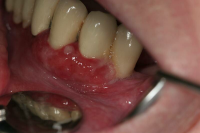

Karakteriseras av approximala nekrotiska och fibrintäckta sår (nedsmälta papiller) som är smärtsamma vid beröring och mycket lättblödande.

Patienten kan ha påverkat allmän tillstånd och ofta foeter ex ore.

I anamnesen förekommer ofta kombination av nedsatt immunförsvar, rökning, stress och dålig munhygien. HIV/Aids kan finnas som bakgrundsfaktor.